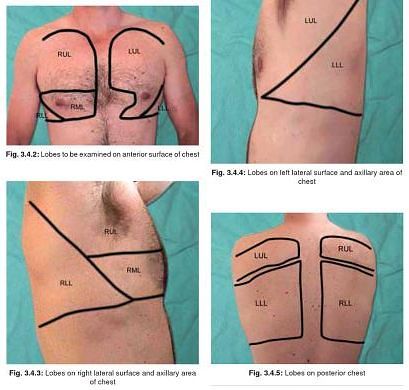

anatomy surface respiratory physiology examination lung relevant lungs lobe ribs middle lower epomedicine fissure upper posteriorly oblique costal sternum floating

Lungs lobes fissures right left oblique both teachmeanatomy lung structure thorax fig similar position info. Pin on bronchial anatomy. Topography of the lungs (posterior view) the apex of the lung extends